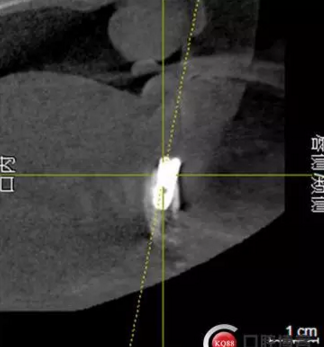

檢查:上頜無(wú)牙頜假牙穩(wěn)定性尚可,下頜3435364243殘根;33殘冠1-2度松動(dòng),其他牙齒缺失;CBCT檢查:下頜牙槽骨前牙區(qū)骨高度足,后牙區(qū)骨高度最低為8mm,骨寬度足。

1)術(shù)前檢查,拍攝臨床照片及CBCT檢查,制取活動(dòng)義齒參考模型,指導(dǎo)后期最終修復(fù)的牙齒排列

2)術(shù)前準(zhǔn)備及手術(shù)過(guò)程,測(cè)量血壓及血糖,簽種植知情同意書(shū);嚴(yán)格遵循無(wú)菌操作,局麻下采用微創(chuàng)技術(shù)于323436分別植入osstem4.0X10,4.0X10,4.5X7; 434446分別植入osstem4.0X1O,4.0X10,4.5X7.初期穩(wěn)定性均達(dá)到了35N.CM以上;嚴(yán)密縫合,止血,種植體位點(diǎn)和方向與設(shè)計(jì)一致。